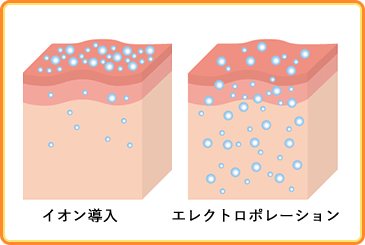

「直接ヒアルロン酸を注入しないのに、本当に効果はあるの?」と思う方もいるかもしれません。

当院が導入している美容機器は、特殊な電気パルスを与えることによって角質層に一時的な隙間を作り、基底層や真皮層に必要な成分を導入します。

そのため針を使わなくても、ヒアルロン酸やコラーゲンを肌深部へ浸透させることが可能です。

エレクトロポレーションとは

電子穿孔理論を美容に応用したものです。

もともとはハーバード大学やマサチューセッツ工科大学などの研究所で開発されていた、遺伝子組織や抗がん剤投与への応用が期待されている最先端技術です。

その安全性から、美容部門ではヒアルロン酸や高分子コラーゲンによる美肌治療だけでなくシミ・肝斑治療、脂肪溶解など、幅広く利用されています。

有効成分の導入率は約16~20倍とも言われ、イオン化できない分子量の大きい成分も効率的に浸透させることができ、安全性にも効果にも優れています。